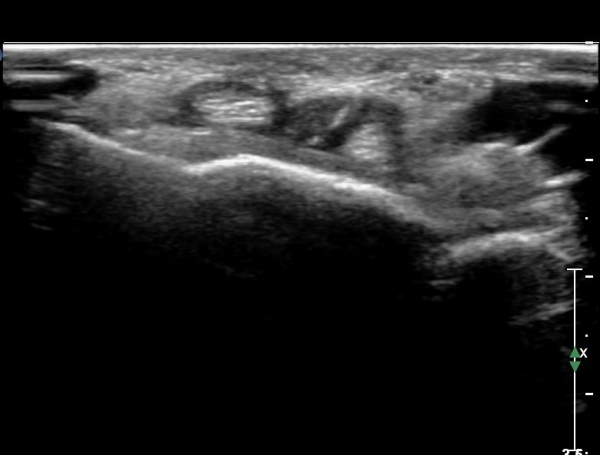

¾Æ·§ÆÈ ÇϺκΠȾ´Ü¸é°Ë»ç¿¡¼­ Àü°ñ°£ ½Å°æ Áö¹è¸¦ ¹Þ´Â  PQ ¿¡¼­ ½Å°æ¸¶ºñ ¼Ò°ß(°í¿¡ÄÚ ±ÙÀ§Ãà)À»

º¸ÀÌÁö ¾ÊÀ¸³ª  FPL ÈûÁÙÀÇ Àú¿¡ÄÚ ºÎÁ¾ÀÌ °üÂûµÇ°í(»çÁø 2, 3) ³»°íÁ¤¹°ÀÌ FPL °ú Á¢ÃËÇϰí ÀÖÀ½ÀÌ °üÂûµÊ(»çÁø 3)